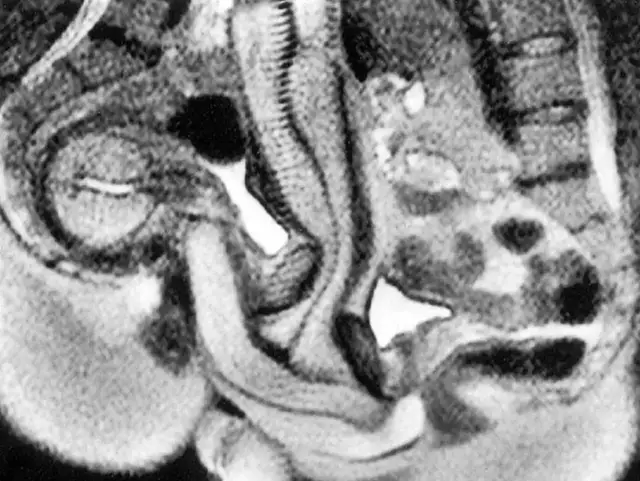

The images produced during the experiment provided remarkable insight into how the body works during intercourse. One of the most surprising discoveries involved the shape of the male anatomy during penetration.

Instead of remaining straight, the images showed that the penis bends inside the vaginal canal. The shape closely resembled a curved or boomerang form. This bending allows the anatomy of both partners to align naturally during intercourse.

This finding contradicted centuries of assumptions that had appeared in early medical drawings and anatomical studies. It also demonstrated that the body adjusts in complex ways during intercourse to accommodate natural movement and positioning.

The MRI scans also revealed new information about how the female body responds during intercourse. Researchers observed changes in the uterus and surrounding structures when arousal occurred.

One key observation showed that during arousal without intercourse, the uterus rises and the front wall of the vagina lengthens. These adjustments prepare the body for intercourse and help accommodate penetration.

However, the scans indicated that the uterus itself does not increase in size during intercourse. This detail helped clarify how female anatomy behaves during the process and corrected several misunderstandings that had circulated in earlier medical discussions.